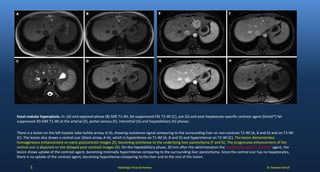

Focal nodular hyperplasia. In- (A) and opposed-phase (B) GRE T1-WI, fat-suppressed FSE T2-WI (C), pre (D) and post hepatocyte-specific contrast agent (Eovist®) fat-

suppressed 3D-GRE T1-WI at the arterial (E), portal venous (F), interstitial (G) and hepatobiliary (H) phases.

There is a lesion on the left hepatic lobe (white arrow, A-H), showing isointense signal comparing to the surrounding liver on non-contrast T1-WI (A, B and D) and on T2-WI

(C). The lesion also shows a central scar (black arrow, A-H), which is hypointense on T1-WI (A, B and D) and hyperintense on T2-WI (C). The lesion demonstrates

homogeneous enhancement on early postcontrast images (E), becoming isointense to the underlying liver parenchyma (F and G). The progressive enhancement of the

central scar is depicted on the delayed post-contrast images (G). On the hepatobiliary phase, 20 min after the administration the hepatocyte-specific contrast agent, the

lesion shows uptake of the contrast agent, becoming minimally hyperintense comparing to the surrounding liver parenchyma. Since the central scar has no hepatocytes,

there is no uptake of the contrast agent, becoming hypointense comparing to the liver and to the rest of the lesion.